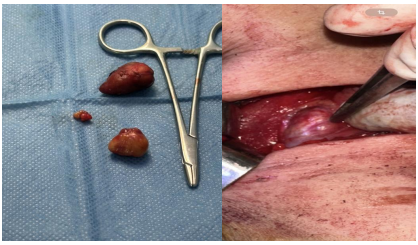

Management included rehydration (4l/D); symptomatic treatment of diuretics and corticosteroids and admitted to the operating room for removal of both parathyroid formations under general anesthesia (figure 3.4); Postoperatively, the serum calcium level decreased to 90 and the patient was extubated with good clinical improvement.

Figure 3.4: Peroperative image of the parathyroid mass on the left, the image of the two removed parathyroid formations